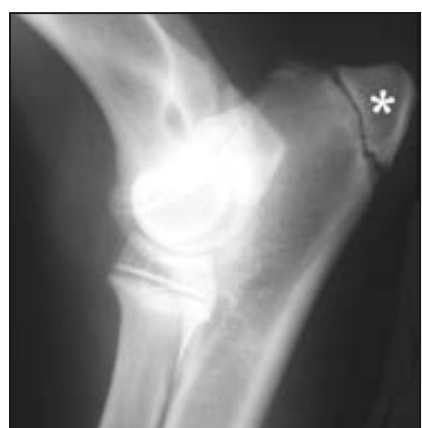

What is the term for the secondary centre of ossification (starred)?

A

Apophysis; additional non-articular cartilaginous protuberances that ossify and form sites of attachment for tendons and ligaments.